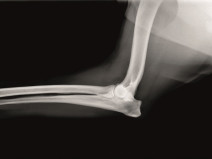

• Soirée l'imagerie du coude

Etre capable de :

• décrire les indications et les limites des différents examens d'imagerie médicale dans la démarche diagnostic des affections du coude

Le 17 mai 2018

BESANÇON (25000)

Imagerie Médicale

Orthopédie

Bourgogne Franche-Comté